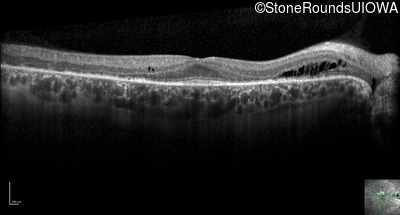

Optical Coherence Tomography - Right - 20/32 +2

Exemplar / OCT Stack